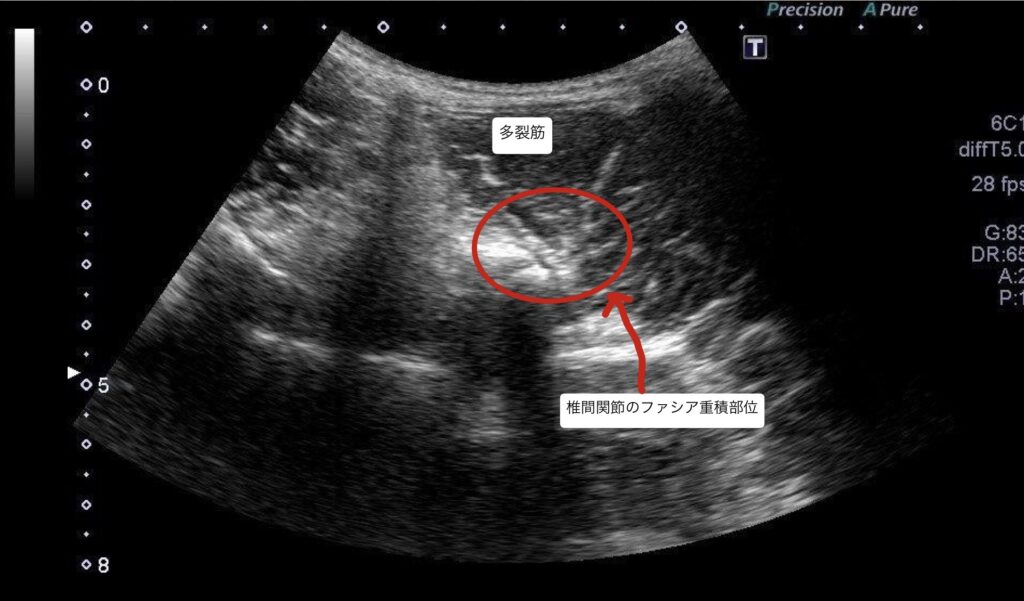

・超音波エコーの観察で、腰椎L4/5番の椎間関節にファシア癒着部位を確認。

・痛みは脊髄神経後枝内側枝周囲の環境悪化、ファシア癒着による痛みの可能性が高い。